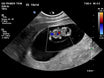

Flujo Tricuspideo

1. Indicador de Anomalías Cromosómicas

Un flujo anormal a través de la válvula tricúspide, como la presencia de regurgitación (cuando la sangre fluye hacia atrás), se asocia con un mayor riesgo de anomalías cromosómicas, como el síndrome de Down (trisomía 21) y otras trisomías. Es un marcador clave que, combinado con otros, ayuda a identificar fetos en riesgo.

2. Detección Temprana de Problemas Cardíacos

La evaluación del flujo tricuspídeo permite detectar signos tempranos de posibles problemas cardíacos congénitos. Una regurgitación significativa puede indicar la necesidad de un seguimiento más intensivo del corazón fetal a lo largo del embarazo.

Ductus Venoso

Indicador de Anomalías Cromosómicas

Un flujo anormal en el ductus venoso durante el primer trimestre puede estar asociado con un mayor riesgo de anomalías cromosómicas, como el síndrome de Down (trisomía 21) y otras trisomías.

Detección Temprana de Problemas Cardíacos

El ductus venoso es un vaso sanguíneo fetal que desempeña un papel clave en la circulación fetal. Un flujo anormal puede indicar problemas cardíacos congénitos, permitiendo una detección temprana y el manejo adecuado del embarazo.